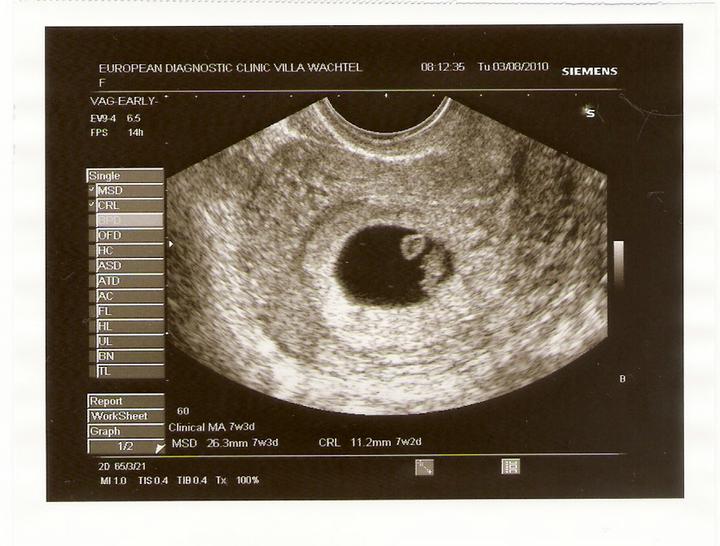

24.8.2010 kontrola u paní doktorky v 11. týdnu - vše je v pořádku, měříme 3,58 cm a dostali jsme novou fotečku.